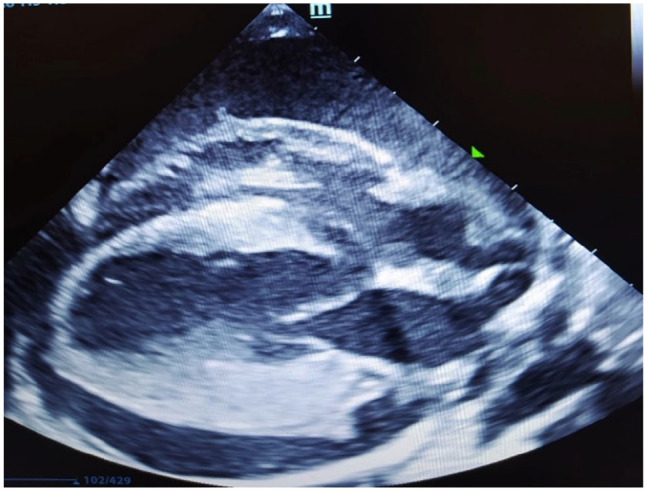

Case summary: A 7-year-old female spayed domestic shorthair cat was presented to our hospital with a 2-day history of anorexia, dyspnoea and lethargy. Blood tests revealed mild anaemia (packed cell volume [PCV] 22.4%) and the biochemistry panel was unremarkable. Thoracic radiographs and echocardiography showed the presence of pericardial effusion with cardiac tamponade as well as pleural effusion. During the initial attempt at pericardiocentesis, a small sample was obtained, sufficient only for fluid analysis and cytology. Subsequently, the pericardial effusion immediately resolved, presumably owing to the drainage of pericardial fluid into the pleural space. Thoracocentesis was then performed, yielding 50 ml of fluid. The analysis of the fluid was consistent with a protein-rich transudate associated with macrophagic-neutrophilic inflammation in both sampled areas. PCR was positive for Bartonella henselae in the pleural/pericardial fluid pool and peripheral blood. Bacterial culture was negative and feline coronavirus real-time PCR was negative. The patient was treated with marbofloxacin 5 mg/kg PO q24h for 5 weeks. No clinical signs were reported at this time; however, blood B henselae PCR remained positive. Treatment was changed to doxycycline at 5 mg/kg PO q12h for 6 weeks. The cat remained subclinical throughout the treatment, and a blood PCR after 6 weeks yielded negative results.

Relevance and novel information:  To the best of the authors' knowledge, the present clinical findings related to B henselae infection in a cat without concurrent heart failure have not been previously documented. This clinical case highlights the need to include Bartonella species as a differential diagnosis in cats with protein-rich transudate effusions associated with neutrophilic-macrophagic inflammation and fever.